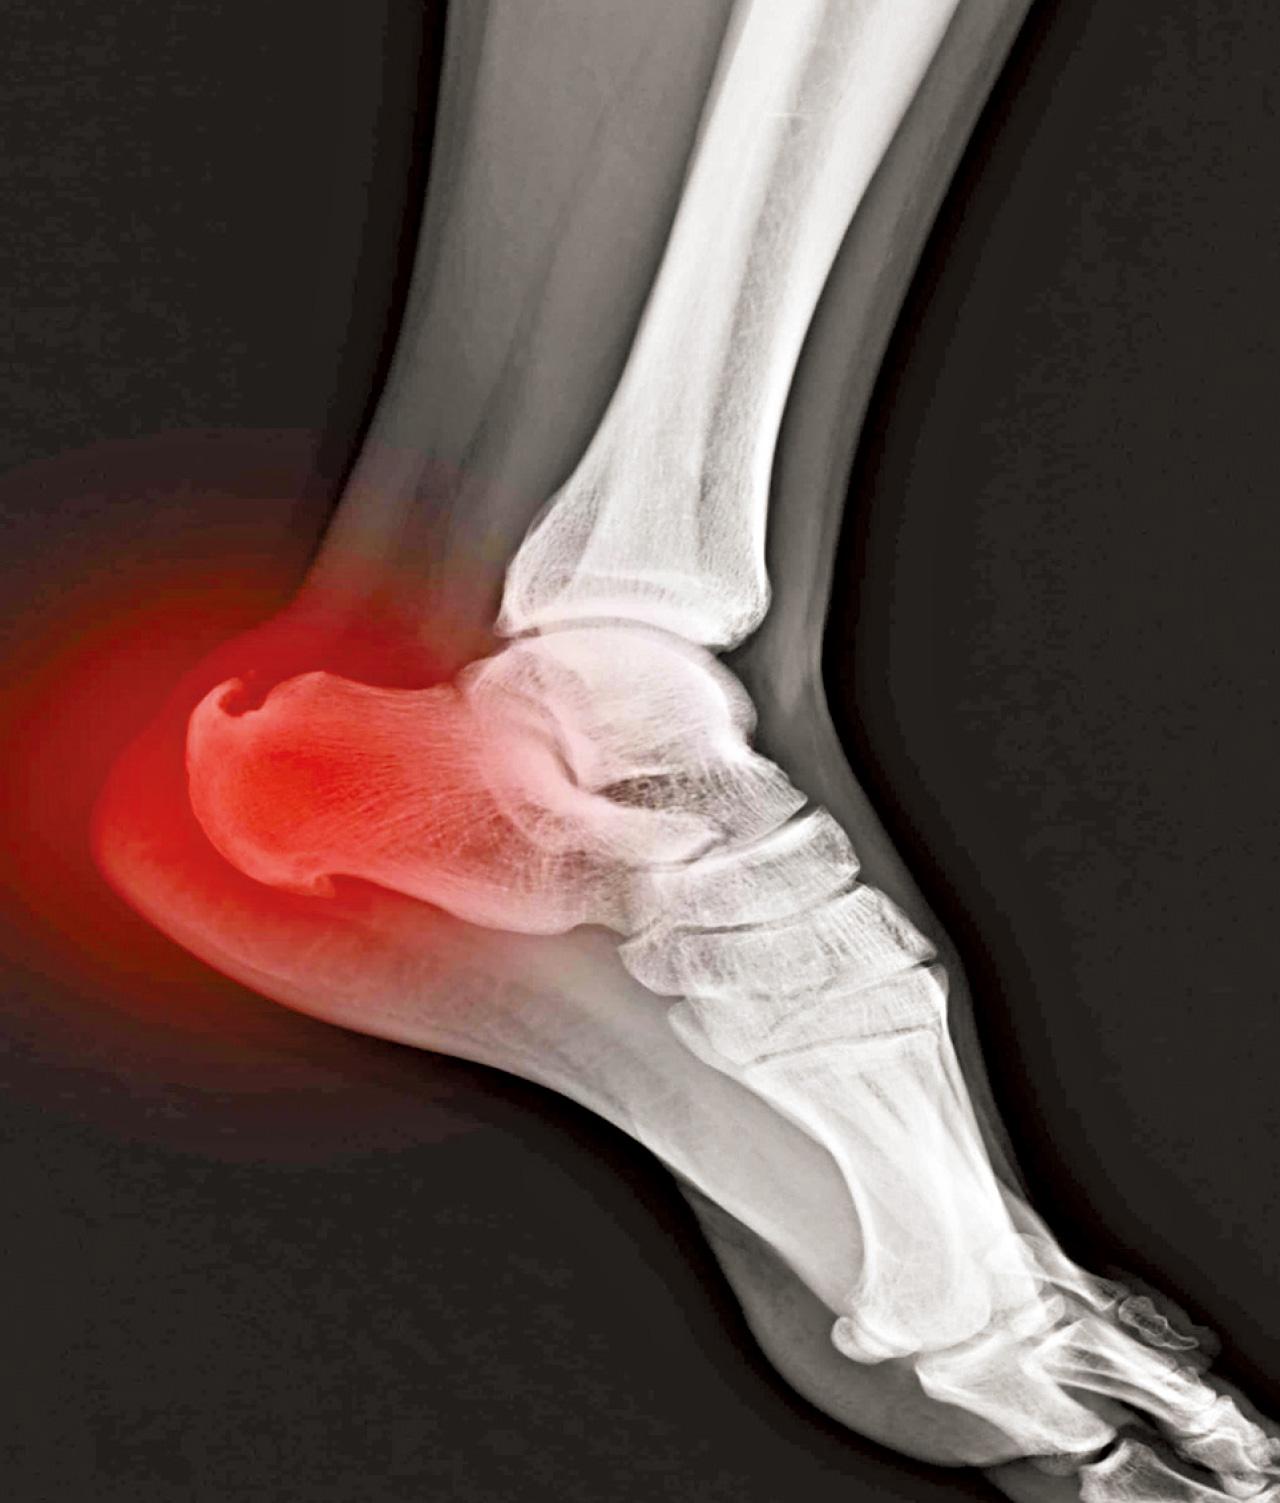

骨刺一般情況不會引起疼痛,大部分情況下,導致長期痛症的原因包括姿勢問題、運動發力錯誤、勞損等,而在關節炎情況比較嚴重時,可能會導致關節面摩擦增多而導致疼痛和活動受限。

為甚麼會有骨刺呢?其實透過觸摸一下雙腳腳眼可略知一二,身體上一些較突出的位置都是由肌肉或韌帶反覆拉扯而形成。而骨刺的形成一樣是因為軟組織經過反覆用力或肌肉繃緊而造成。所以,其實骨刺是伴隨著大量軟組織繃緊及勞損問題。